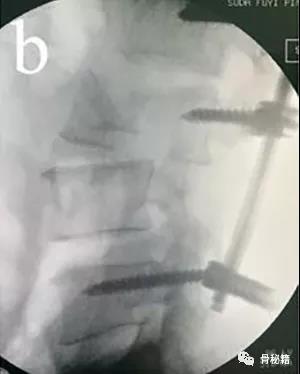

先植入能植入的椎弓根螺钉, 深度过椎弓根即可

先进行短阶段的撑开,撑开之后暴露关键的前移的椎体再植入椎弓根螺钉进行二次撑开

要点:进行初次撑开之后,取下一侧的棒,植入关键椎体的椎弓根螺钉再换另外一侧,同法。